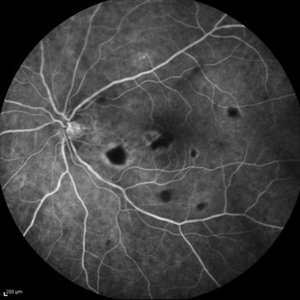

Best Disease Best DiseaseMar 9 2013 by Hamid Ahmadieh, MD FA and ICG Angiography of the left eye of a 49-year-old man with advanced Best disease. Photographer: Soodabeh Fooladin, Negah Eye Center, Tehran Imaging device: Heidelberg Spectralis Condition/keywords: Best disease, indocyanine green (ICG) angiography